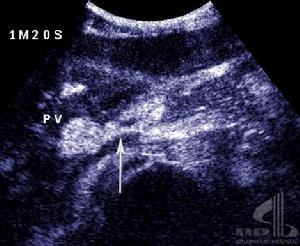

肝移植術1.3術後監測及數據形成計算出血患者移植術前終末期肝病模式(modelforend-stageliverdisease,MELD)評分,記錄腹腔出血患者術後每天腹腔引流液量(作為出血量),根據情況給予動態監測血常規、凝血情況(包括凝血酶原時間PT、國際標準化凝血時間INR、部分凝血活酶時間aPTT及纖維蛋白原Fbg),記錄移植術中及移植術後出血量(其中手術止血者包括手術中出血量及引流量)、輸血量,移植術中總入量、總出量和液體平衡量,並根據出入量計算術中和術後頭3天液體總平衡量。出血停止後給予行腹腔彩色超聲檢查明確腹腔積血及肝臟血運情況。

肝移植術2.2出血患者一般情況出血患者共10例,發病率11.5%(10/87);死亡4例,病死率40%(4/10)。基礎疾病分別為慢性B肝肝硬化合併肝癌(5例),慢性肝炎肝硬化合併肝性腦病(2例),慢性重型肝炎(2例),慢性肝炎肝硬化合併門脈高壓、脾功能亢進(1例)。其中採取保守治療5例,5例患者經保守治療後出血得到控制,其中1例治癒無併發症、4例並發MODS死亡,其中加用重組活化凝血因子Ⅶ者3例(其中1例出現肝動脈血栓);採取手術患者5例,其中用重組活化凝血因子Ⅶ者無效後手術者2例,手術時發現出血部位分別為膽管動脈吻合口處小動脈(2例)、手術區肝膽外的小動脈(2例)、肝動脈吻合口處小滋養動脈(1例),均治癒無其他併發症出現。

3.2手術因素包括未止血的痙攣血管解痙後出血,縫扎線松解、脫落後出血,供肝包膜血管及腹壁等血管未妥善止血,徹底止血後血栓脫落等,這種出血多為動脈性出血,一般靠補充血小板、凝血因子及凝血酶原等不能糾正,手術探察多可發現出血血管,需再手術治療。本研究中5例患者經補充血小板、凝血酶原等後不能糾正,而行剖腹探查術,而手術止血後徹底止血則屬此類,且手術中證實出血部位均為動脈,分別為膽管動脈吻合口處小動脈2例、手術區肝膽外的小動脈2例、肝動脈吻合口處小滋養動脈1例。